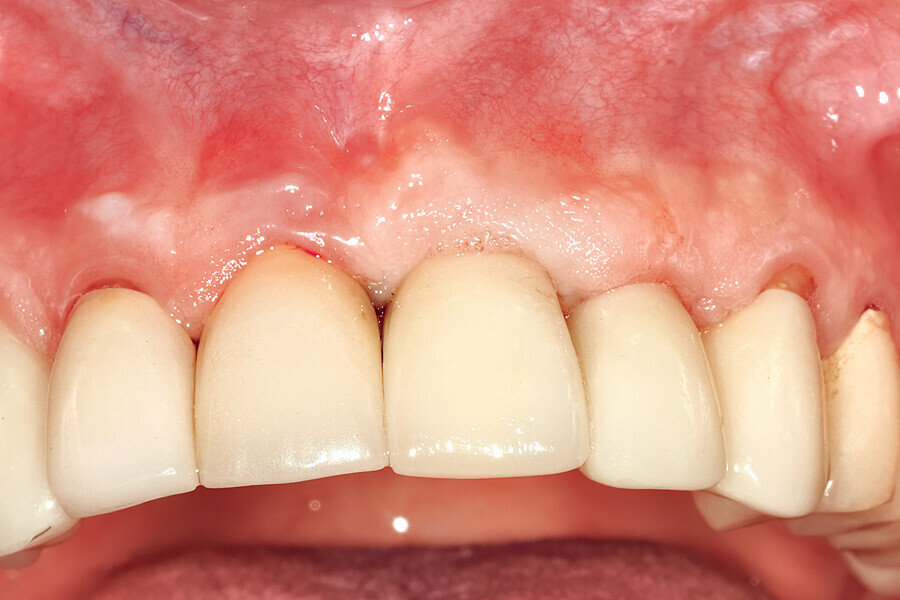

Fig. 26d: The soft-tissue contours were excellent; no sutures were required for the transitional restoration.